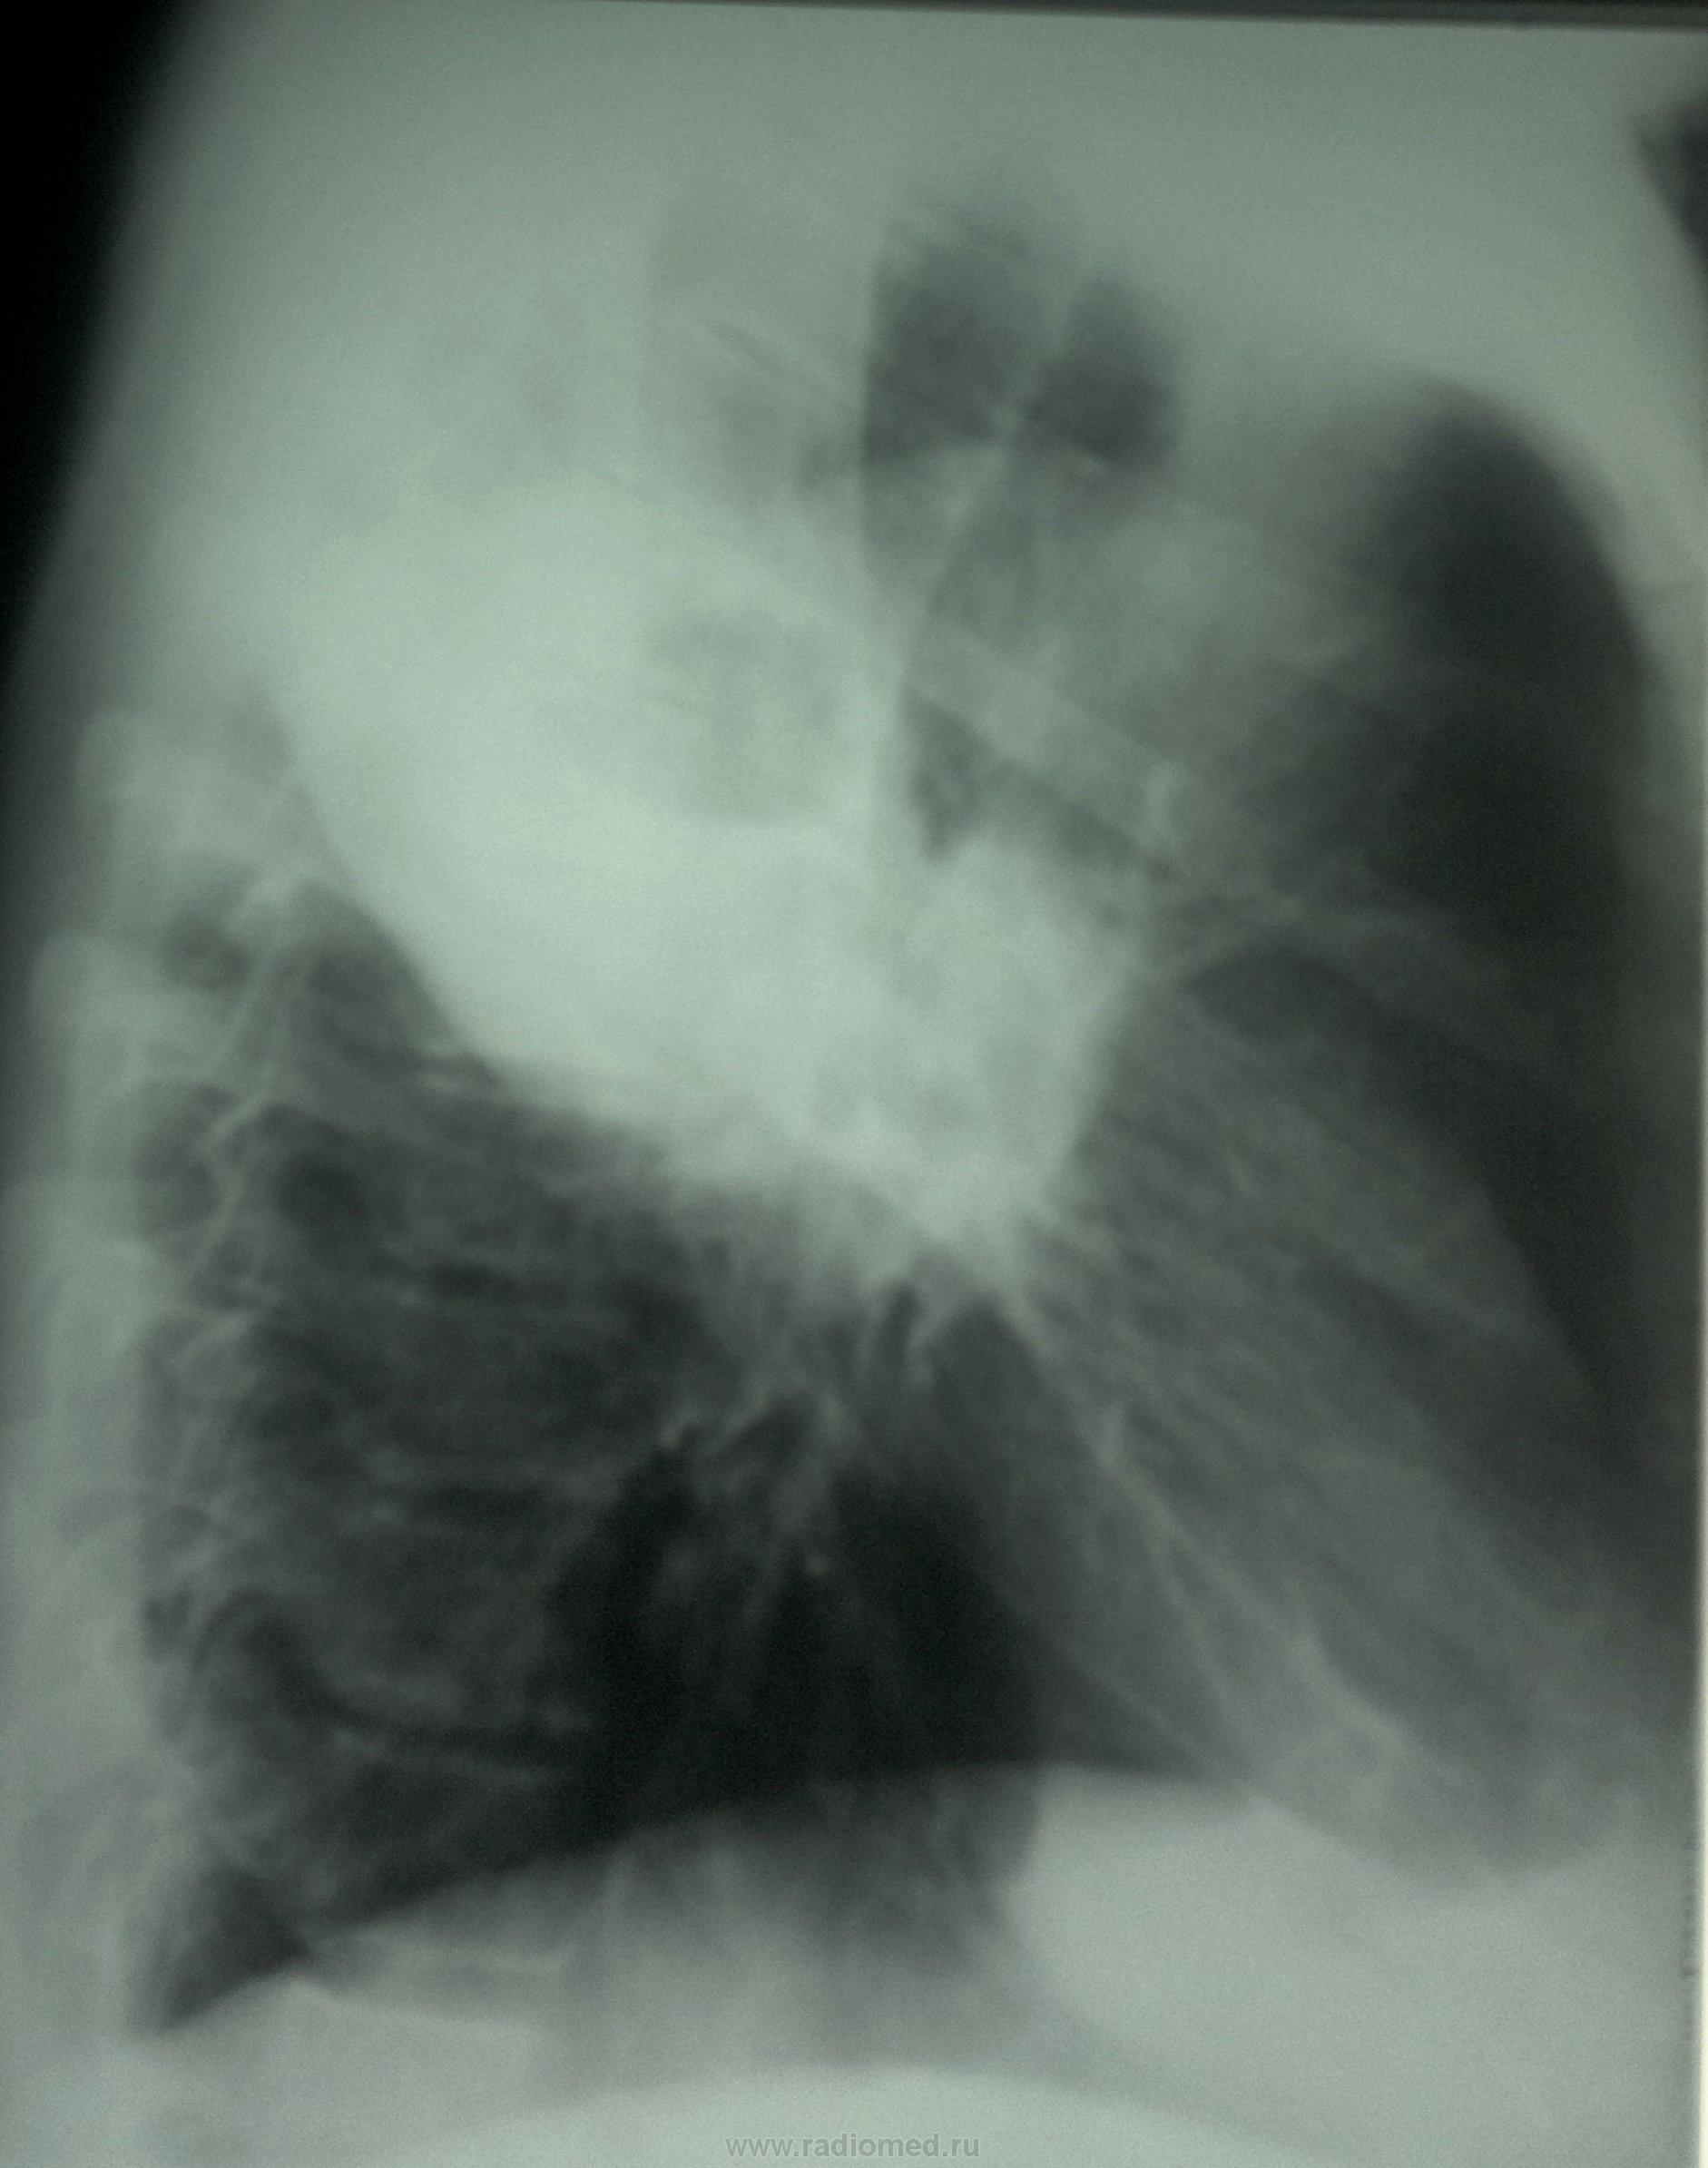

Контроль от 18.12.13

Заложили в т\о. Клиники особенной нет. (кашель с небольшим количеством мокроты).

Контроль от 27.12.13

Выставил: Абсцедирующая пневмония в\доли правого легкого. Смущает отсутствие динамики.